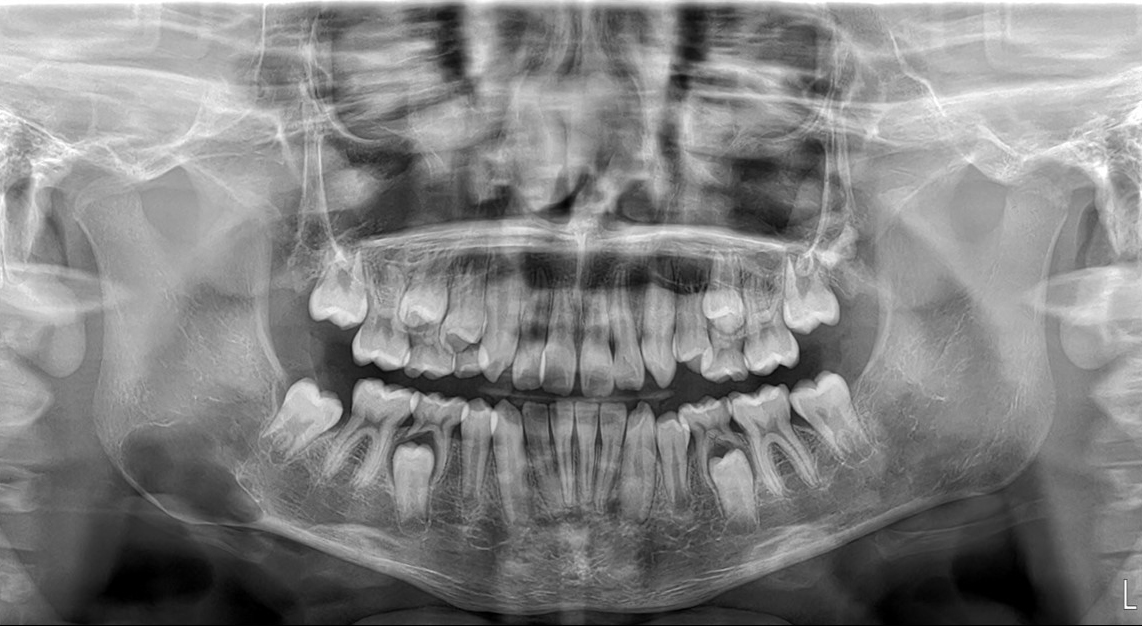

Caso Clinico N° 742 TERCEROS MOLARES IMPACTADOS

21 Ago 2025